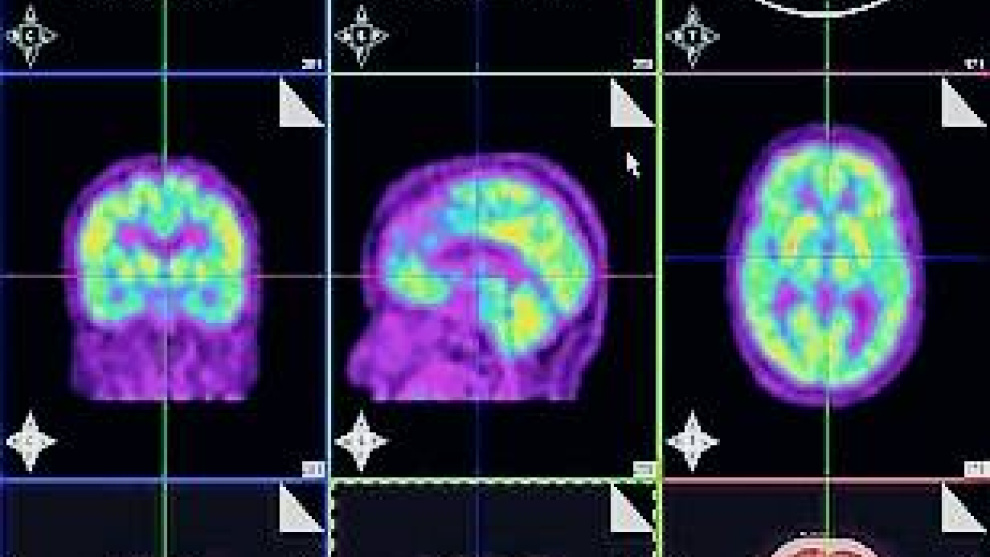

Según se publica en la última edición de JAMA, la inyección de la nueva molécula en los pacientes antes de que se les realizara una prueba de diagnóstico por imagen, un PET, localizó en la imagen cerebral la presencia de la proteína beta-amiloide, lo que se corroboró al hacer la autopsia a los 29 participantes sospechosos de tener alzhéimer después de su muerte.